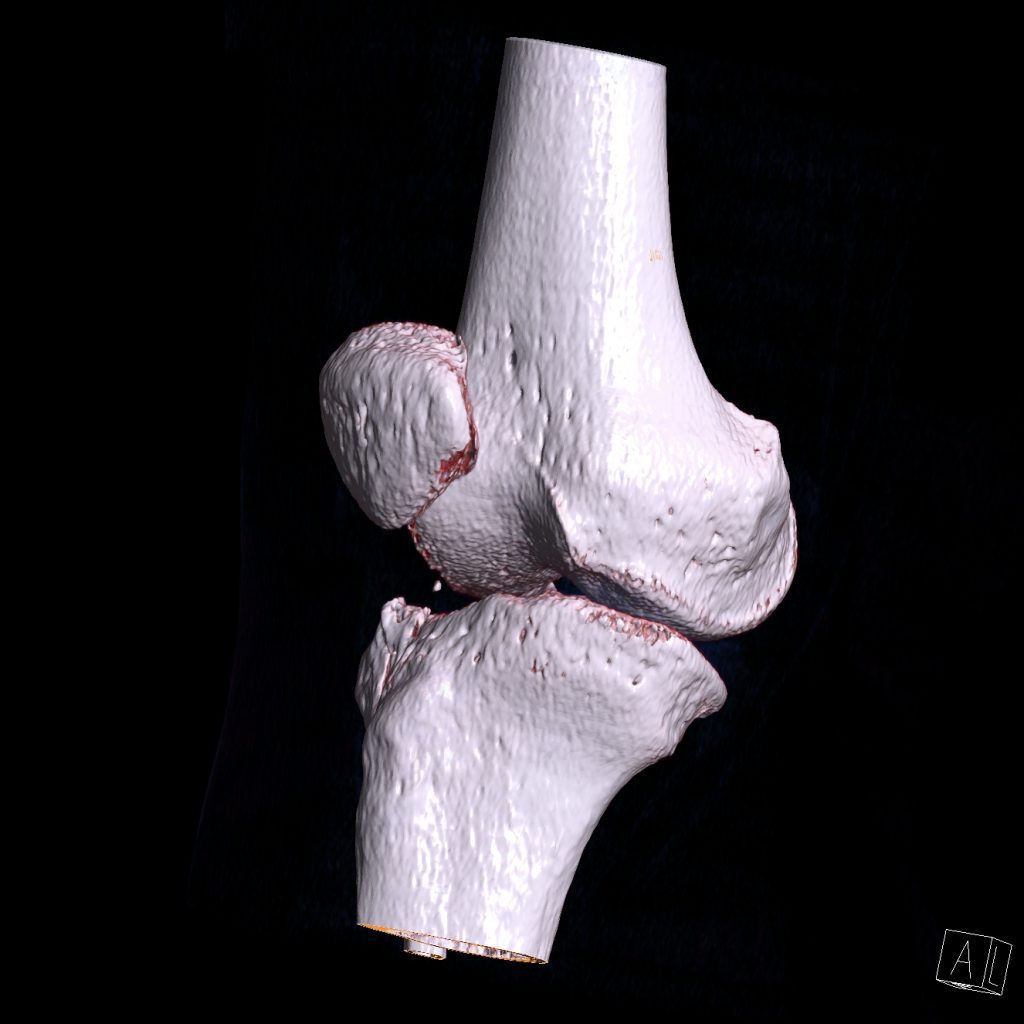

سي تي اسکن اسپيرال زانوي راست ( مولتي ديدکتور 16 با مقاطع ظريف و بازسازي هاي ساژيتال و کرونال و 3D):

– دفورميتي پلاتوي لترال تيبيا ناشي از depressed Fx و فرورفتگي در سطح مفصلي پلاتوي لترال

– نشانه هاي cortical Fx بدون جابجايي در کنديل لترال فمور

– loose body استخواني به ابعاد mm 2 x 3 در انترولترال مفصل زانو و

– افيوژن خفيف در مفصل زانو همراه با تورم نسج نرمي در اطراف آن

مشهود است .